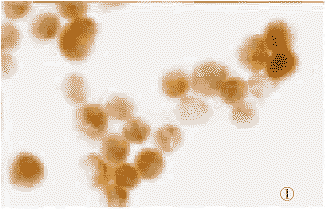

免疫组化检测结果显示,L-CNE1细胞系的LMP1呈强阳性反应,V-CNE1和CNE1细胞系均为阴性;大部分L-CNE1细胞的CD23呈中等强度阳性反应,而V-CNE1和CNE1细胞系均为阴性;L-CNE1、V-CNE1和CNE1细胞系均见少数细胞的bcl-2呈强阳性反应,阳性率为2%~3%,三种细胞系的阳性率无统计学差异(P>0.05)。而各种检测中用TBS代替一抗的阴性对照组全为阴性(图1~4)。

图1 L-CNE1细胞胞浆和胞膜LMP1阳性(棕黄色)。LSAB法 ×400

图2 L-CNE1细胞胞浆CD23阳性(棕黄色)。LSAB法 ×400

图3 鼻咽癌细胞胞浆和核膜bcl-2阳性(棕黄色):

图中仅见少数(2个)阳性细胞,L-CNE1、V-CNE1和CNE1细胞的阳性率相近。LSAB法×400

图4 TBS代替一抗的阴性对照的鼻咽癌细胞

(无棕黄色)。LSAB法×400